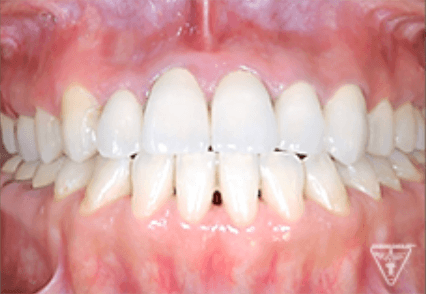

治療後